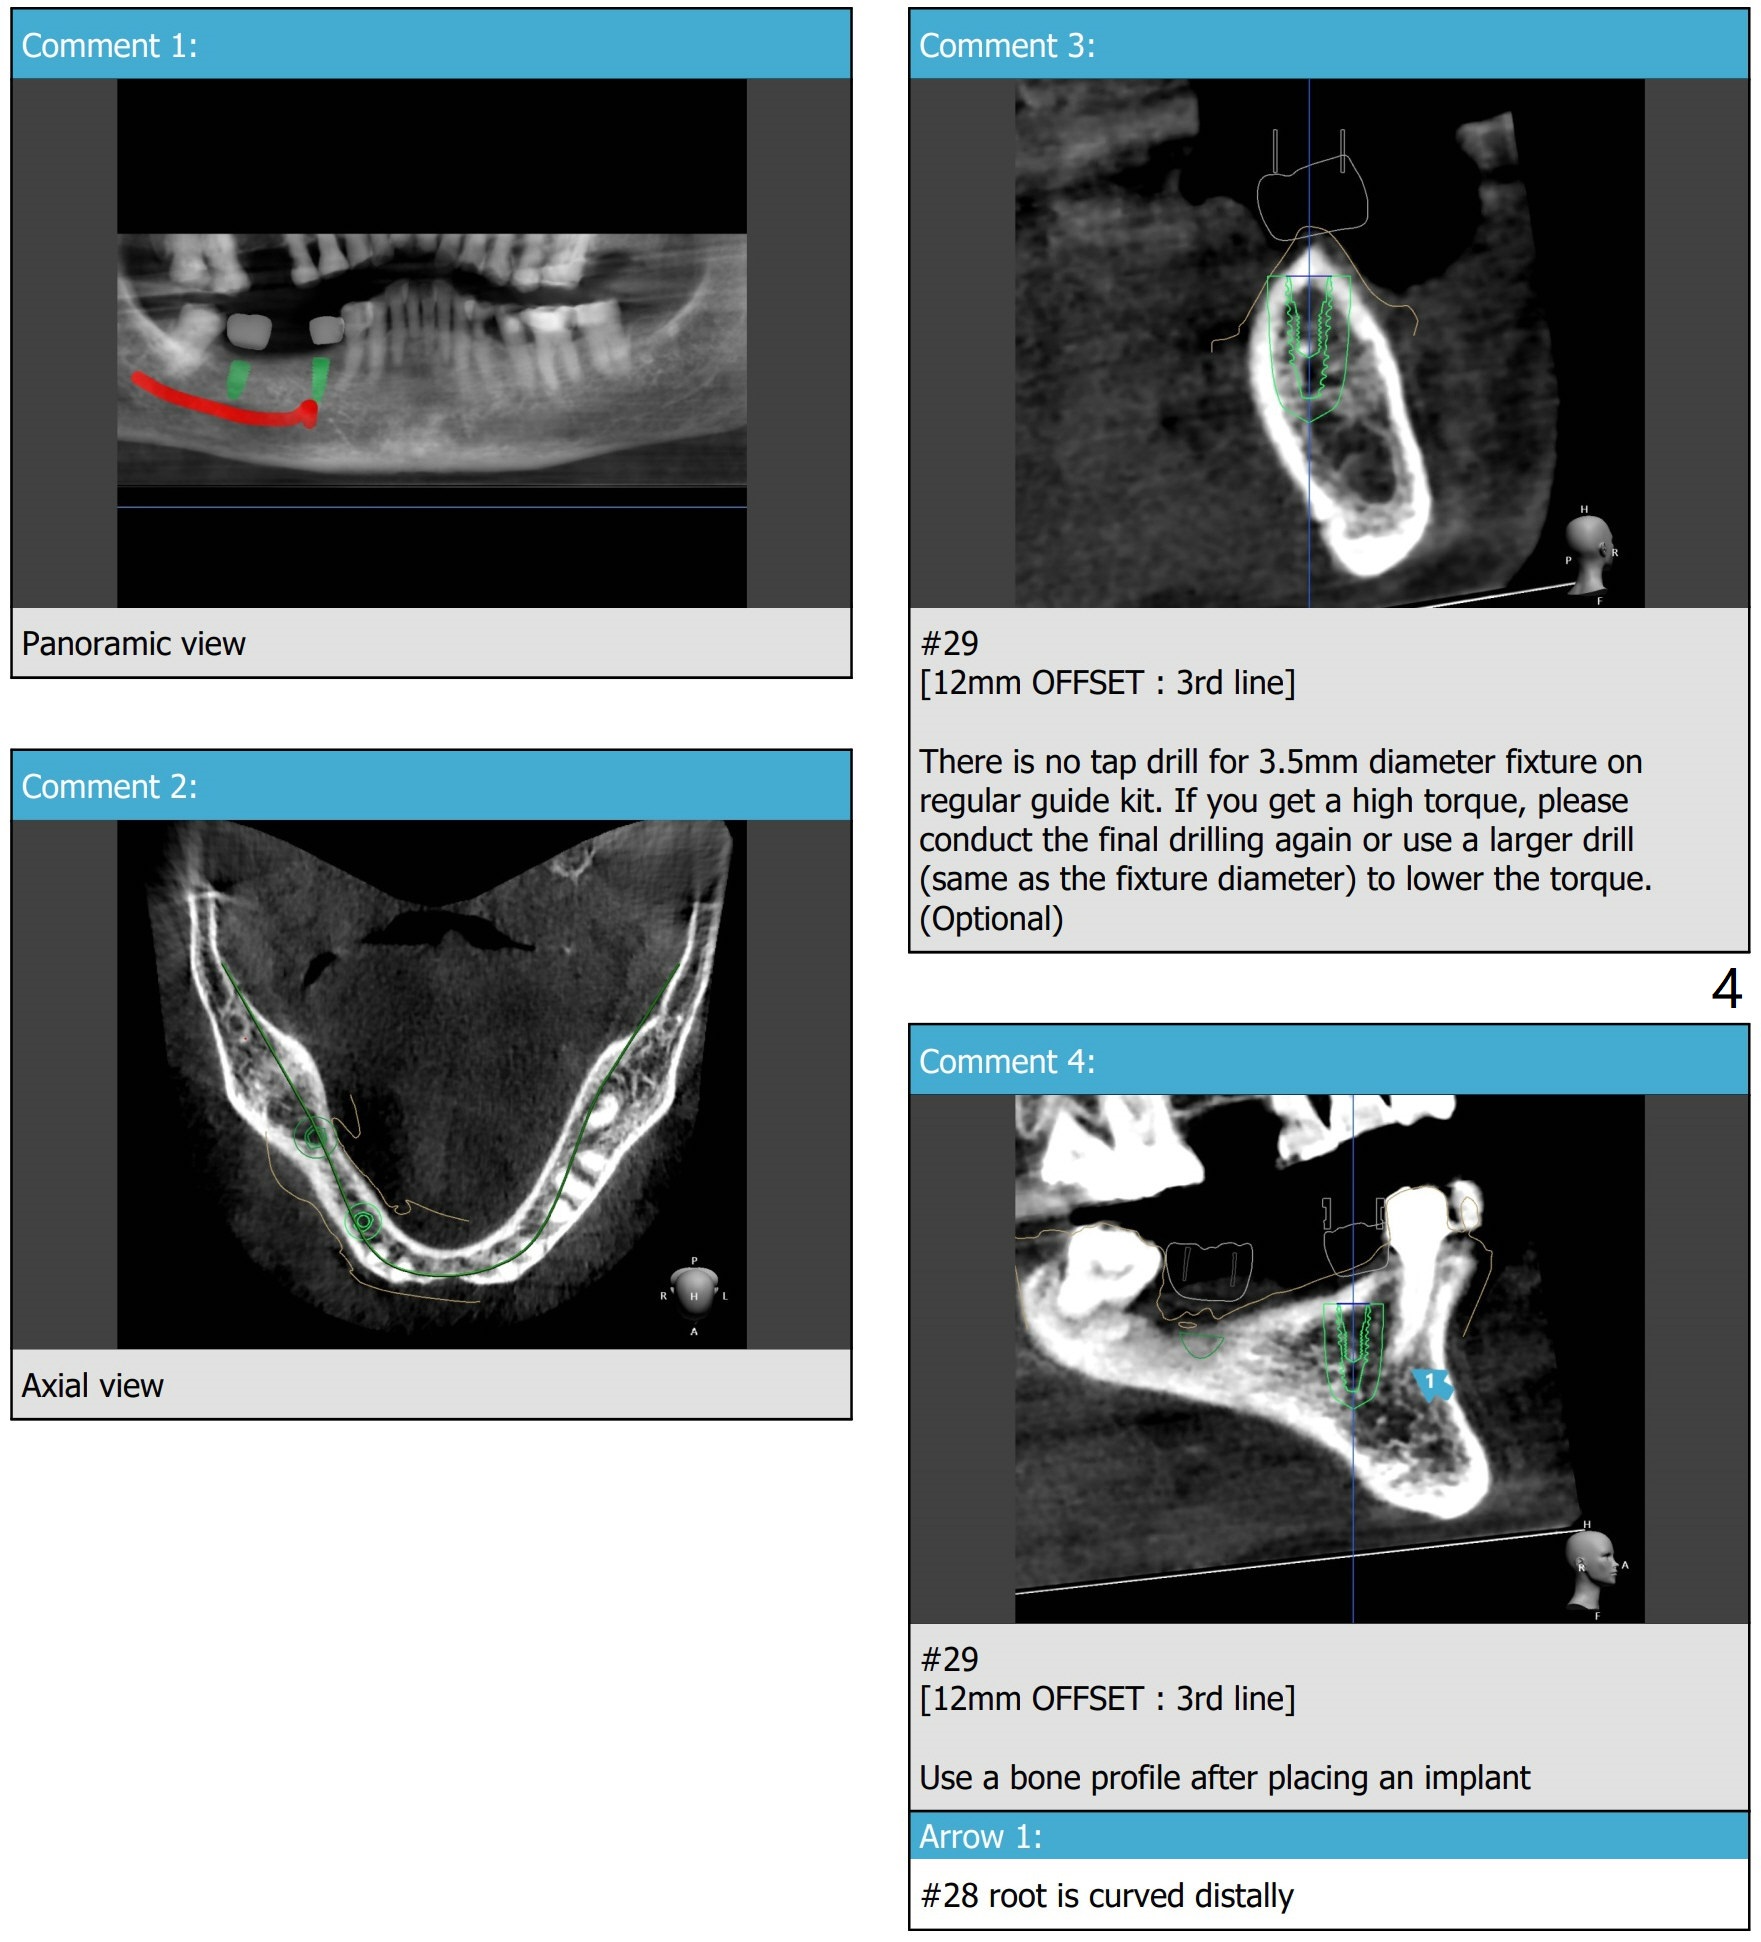

Implant FPD: Design 1

A 81-year-old woman wants to eat well.  #3, 15, 29-31 are missing.